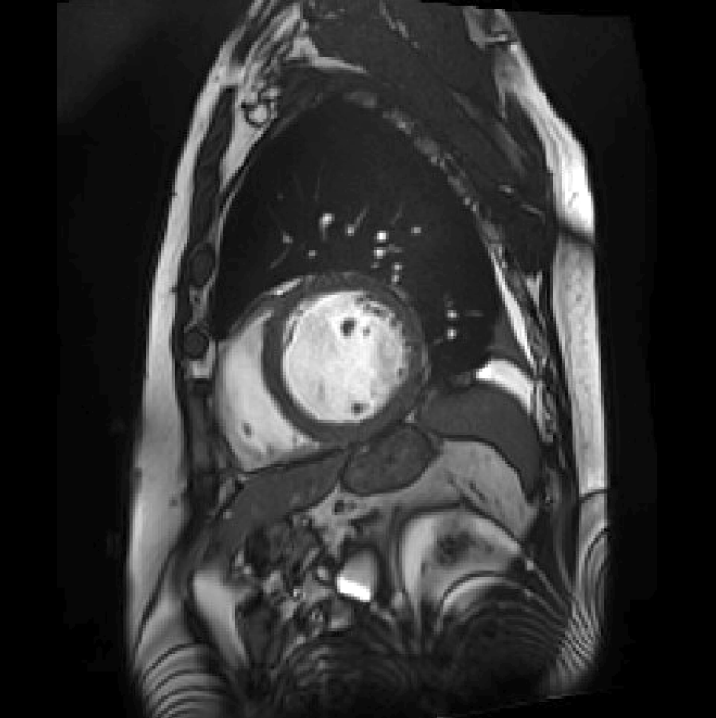

(c) [Uncaptioned image] This image is a sagittal MRI scan of the thoracic region, prominently displaying the heart and surrounding structures. The heart is centrally located, with its chambers and major blood vessels visible, including the aorta. The lungs, with their branching bronchial structures, can be seen around the heart. The vertebral column runs vertically along the left side of the image, providing structural support and orientation. The grayscale contrast highlights different tissue densities, aiding in distinguishing between various anatomical features. This detailed imaging is crucial for diagnosing cardiovascular and thoracic conditions.

(e) [Uncaptioned image] This image is a sagittal MRI scan of the abdomen, showcasing various internal structures in detail. Central to the image is a large, circular organ, likely the liver, with its characteristic texture and surrounding tissues. The diaphragm is visible, delineating the boundary between the thoracic and abdominal cavities. The vertebral column is seen running vertically along the left side, providing a reference point for orientation. The grayscale contrast highlights different tissue densities, facilitating the diagnosis and evaluation of abdominal conditions.